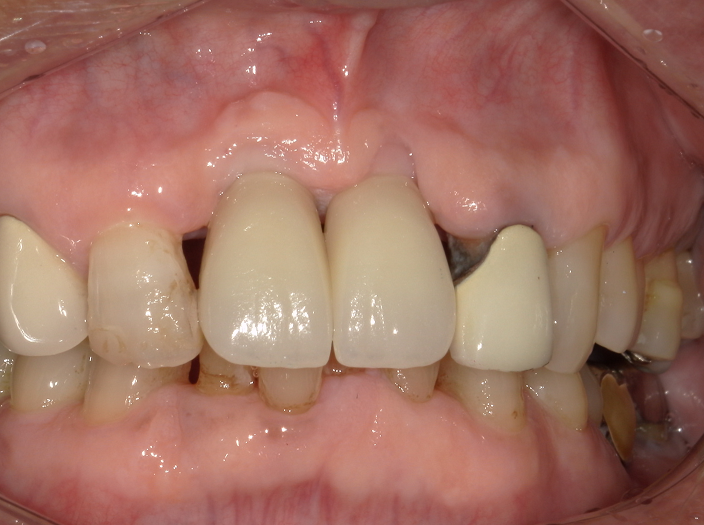

この方はかなり 御高齢の男性で 前歯がほぼ自然に取れて来る状態になりました。

下の前歯が上の 歯肉にまで噛み込む 噛み合わせだったので、部分入れ歯を作ることにも不可能だったのです。

そこで 100パーセント満足し教科書的な立派な治療ではないけれども 、私の技術を持ってなんとかインプラントができます。少なくとも 取り外しはしなくてよい形で 前歯を作ることができますと提案しますと、患者さんはそれではお願いしますといったこととなりました。

(少ない骨でもインプラントの先端を鼻腔底に一部噛ませることで強く固定を取っている、これができるか否かがこの症例のキーです)

上がインプラント後3か月めです。4か月後には歯が入りました。

下が装着したところ。

周囲の歯で今後治療が必要なところは順次行っていきます。

歯科医師が見れば もしかしたら多少 無理をしたケース かもしれません。しかし私は最大限 患者さんの希望を叶えられるよう 医学的にはある程度妥協しながらでもなんとか治療をしたつもりです。